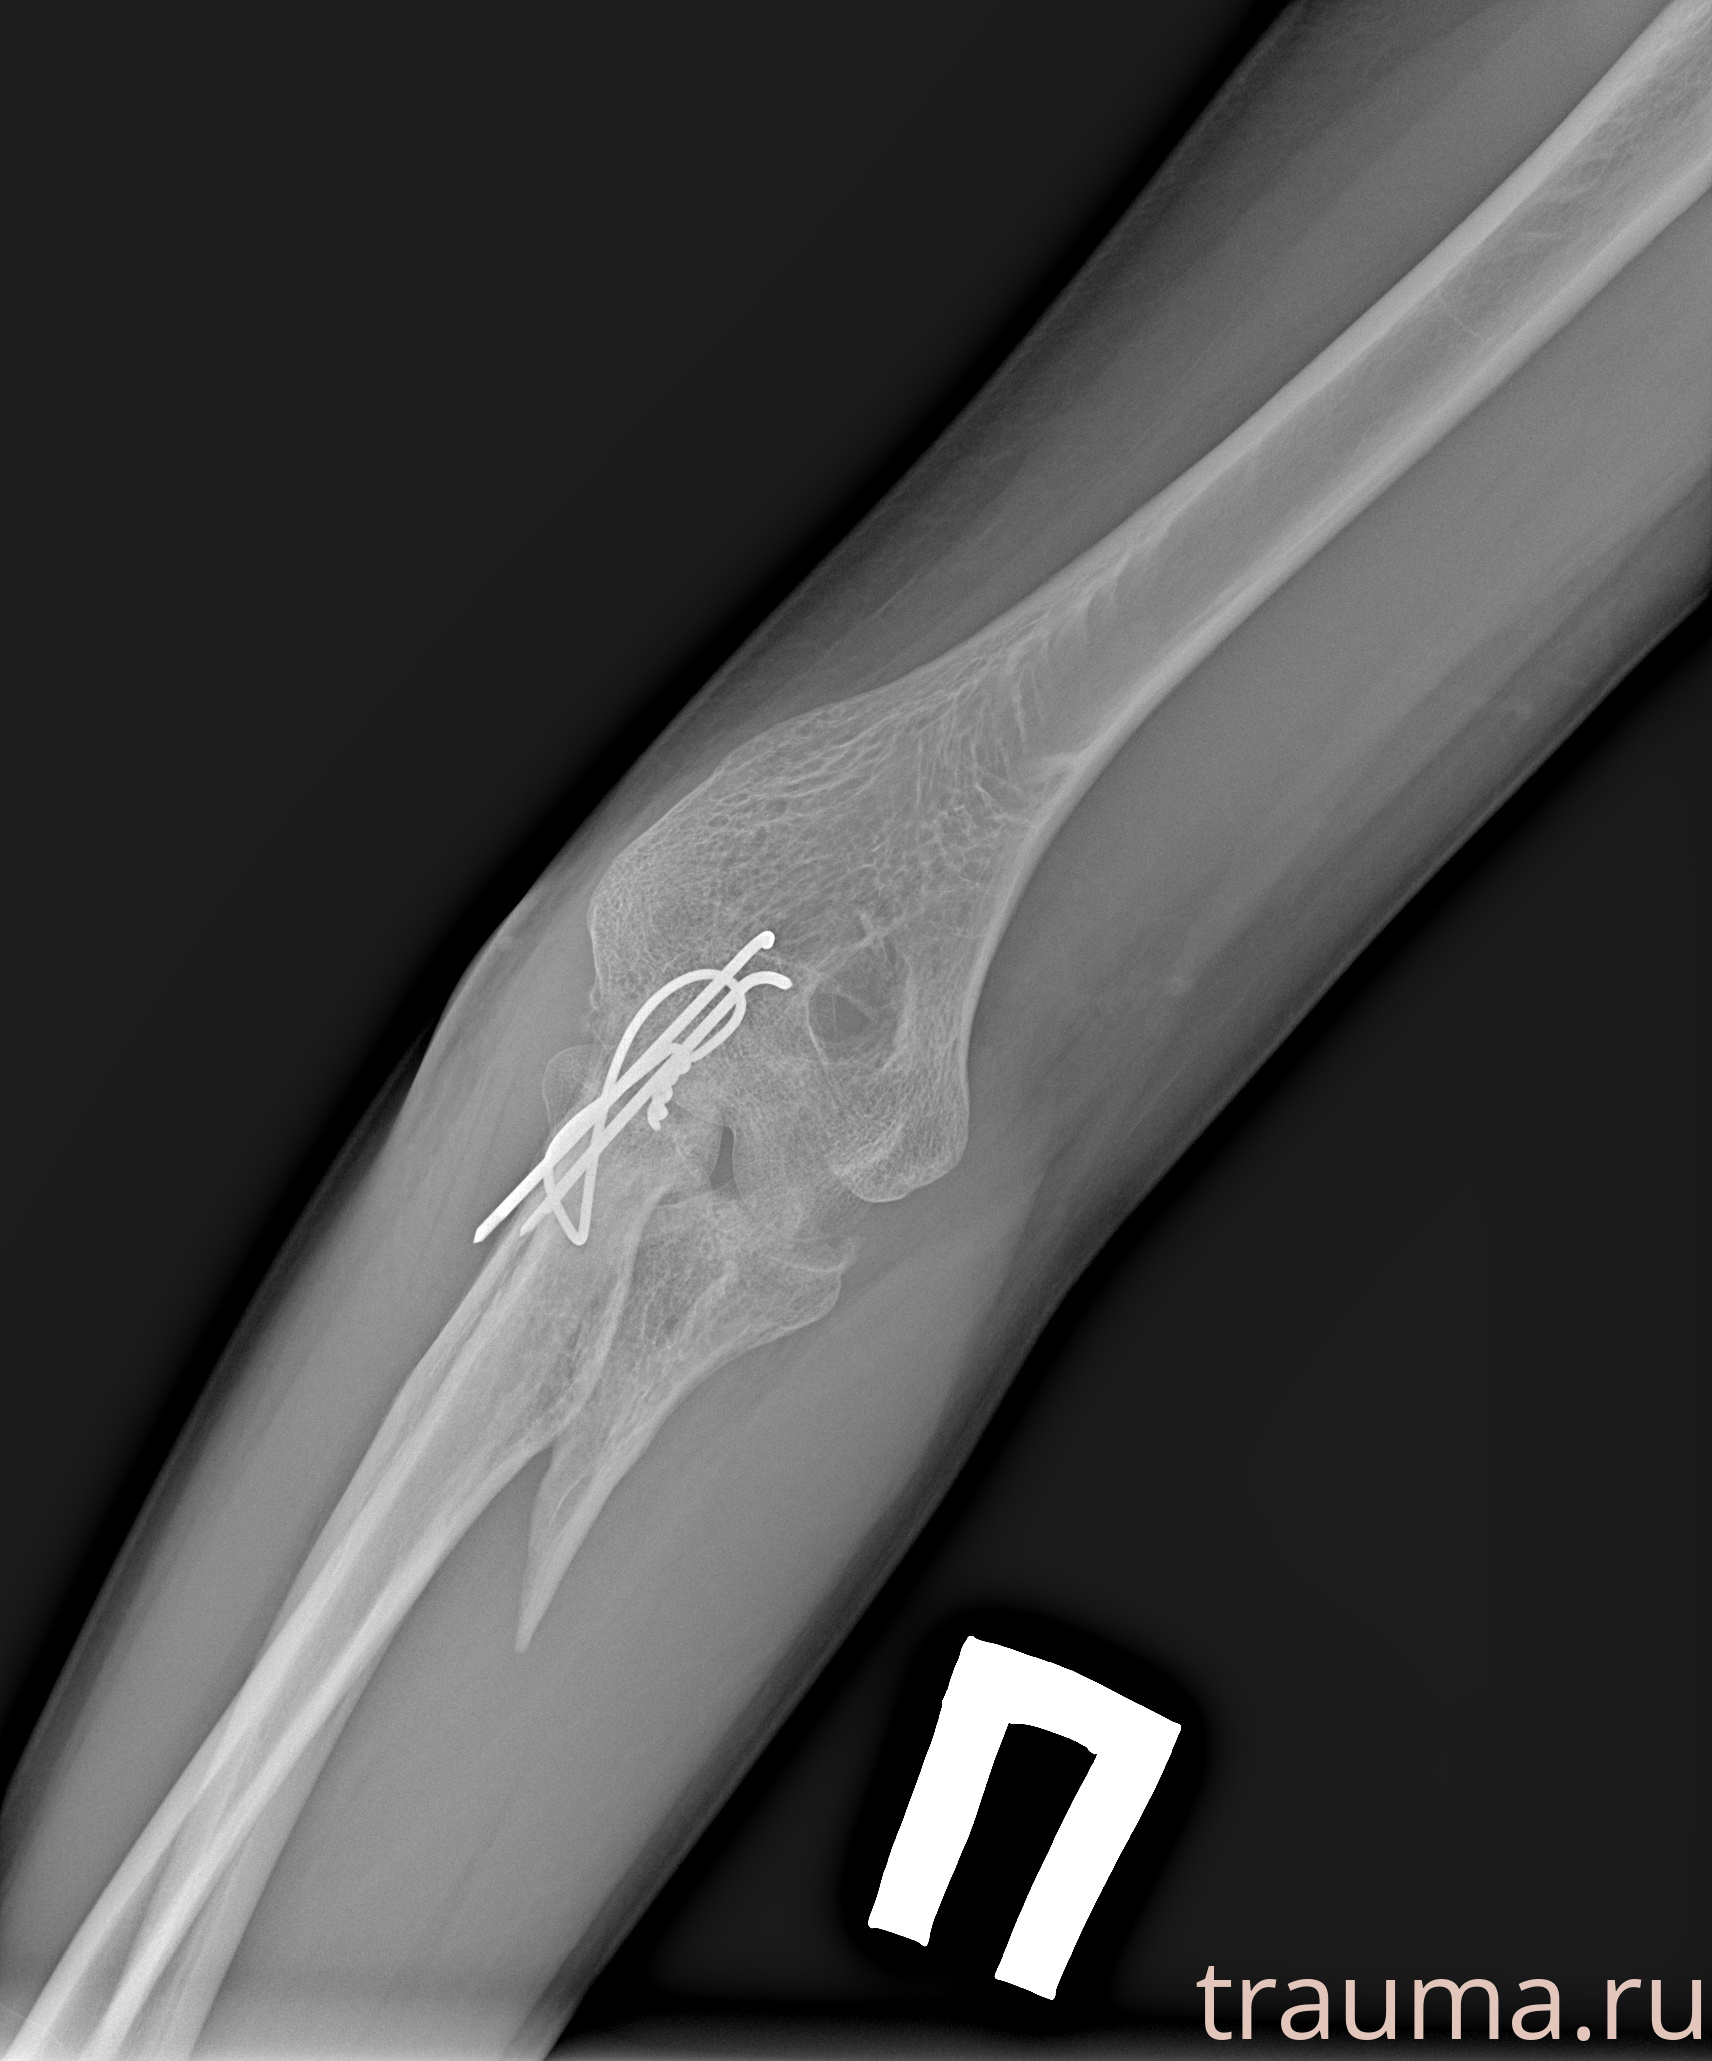

Рентген на дому: по вашему адресу приезжает врач-рентгенолог, травматолог-ортопед с мобильным рентгеновским аппаратом, проводит диагностику травмы или заболевания, делает необходимые рентгенограммы, дает рекомендации по дальнейшему лечению. Получить качественные снимки в домашних условиях возможно благодаря уникальной методике, разработанной МосРентген Центром для института  Склифосовского